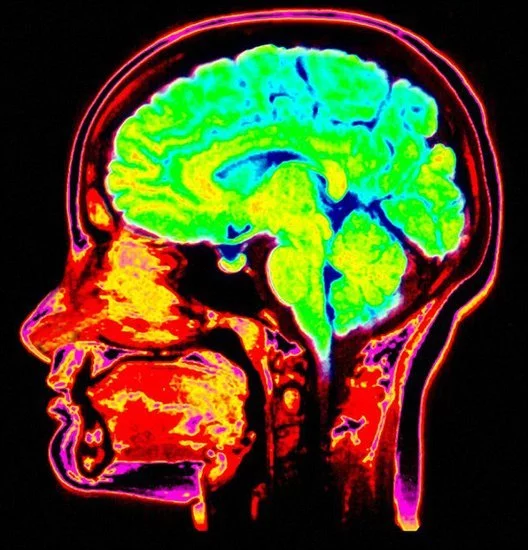

大脑扫描器是一种可以扫描整个大脑的仪器。

科学家最新研制出大脑扫描器 或将完全来自复制人们的梦境。马克斯-普朗克协会360百科科学家证实扫描神智清晰造梦者大脑的梦境就像扫描其清醒状态大脑思维一样,这项最新研究发表在《当代生物学》杂志上,可用于展示建立动态人类大脑梦境图像的"复原技术"。

科学家使用核磁共振成像和近红外线光谱仪来监控造梦者头部的热量变化,从而显示出大脑活跃性。当造梦者做梦时并未紧握手,但大脑扫描可以显示当他们紧握真实手和梦境虚幻手时大脑活跃性特征。